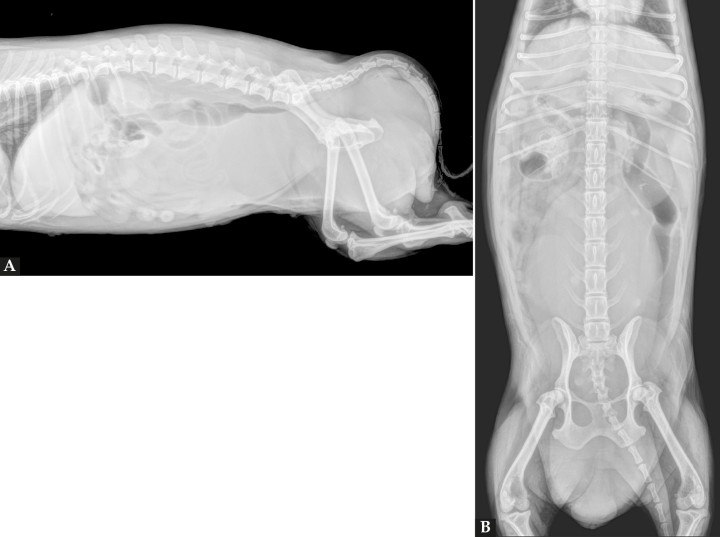

En las proyecciones lateral derecha (Fig. 2A) y ventrodorsal (Fig. 2B) se identifica en el abdomen medio y caudal una estructura de opacidad tejido blando, de morfología ovalada y márgenes redondeados, que se extiende desde el nivel de L1 hasta caudal al canal pélvico, desplazando a la vejiga de la orina craneoventralmente, al intestino delgado hacia craneal y al colon descendente y recto dorsalmente, causando una compresión marcada de estos últimos. La región perineal mostraba un aumento del espesor de los tejidos blandos. El parénquima hepático presentaba un leve aumento de su tamaño, excediendo el arco costal, con bordes lisos y afilados. A nivel de la vesícula biliar se observa una estructura radiopaca compatible con un colelito biliar, así como múltiples renolitos bilaterales.

<p>Mismas radiografías que la Figura 1. Nótese en el abdomen medio y caudal una masa opacidad tejido blando de morfología ovalada y márgenes redondeados (flechas negras). La masa genera un desplazamiento craneoventral de la vejiga de la orina (flechas blancas) y comprime al colon descendente y al recto dorsalmente (flechas rojas). Aumento del espesor de los tejidos blandos en la región perineal (flechas verdes). Además, se observanmúltiples renolitos bilaterales (flechas amarillas) y un colelito biliar (flecha azul).</p>

Mismas radiografías que la Figura 1. Nótese en el abdomen medio y caudal una masa opacidad tejido blando de morfología ovalada y márgenes redondeados (flechas negras). La masa genera un desplazamiento craneoventral de la vejiga de la orina (flechas blancas) y comprime al colon descendente y al recto dorsalmente (flechas rojas). Aumento del espesor de los tejidos blandos en la región perineal (flechas verdes). Además, se observanmúltiples renolitos bilaterales (flechas amarillas) y un colelito biliar (flecha azul).

La imagen radiográfica es compatible con una masa en abdomen medio y caudal con extensión hacia el canal pélvico y región perineal. Los diagnósticos diferenciales incluyen una patología de vagina/útero (neoplasia, granuloma o piometra). Una masa a partir del recto no puede ser descartada (neoplasia, absceso, granuloma), siendo otros orígenes menos probables.